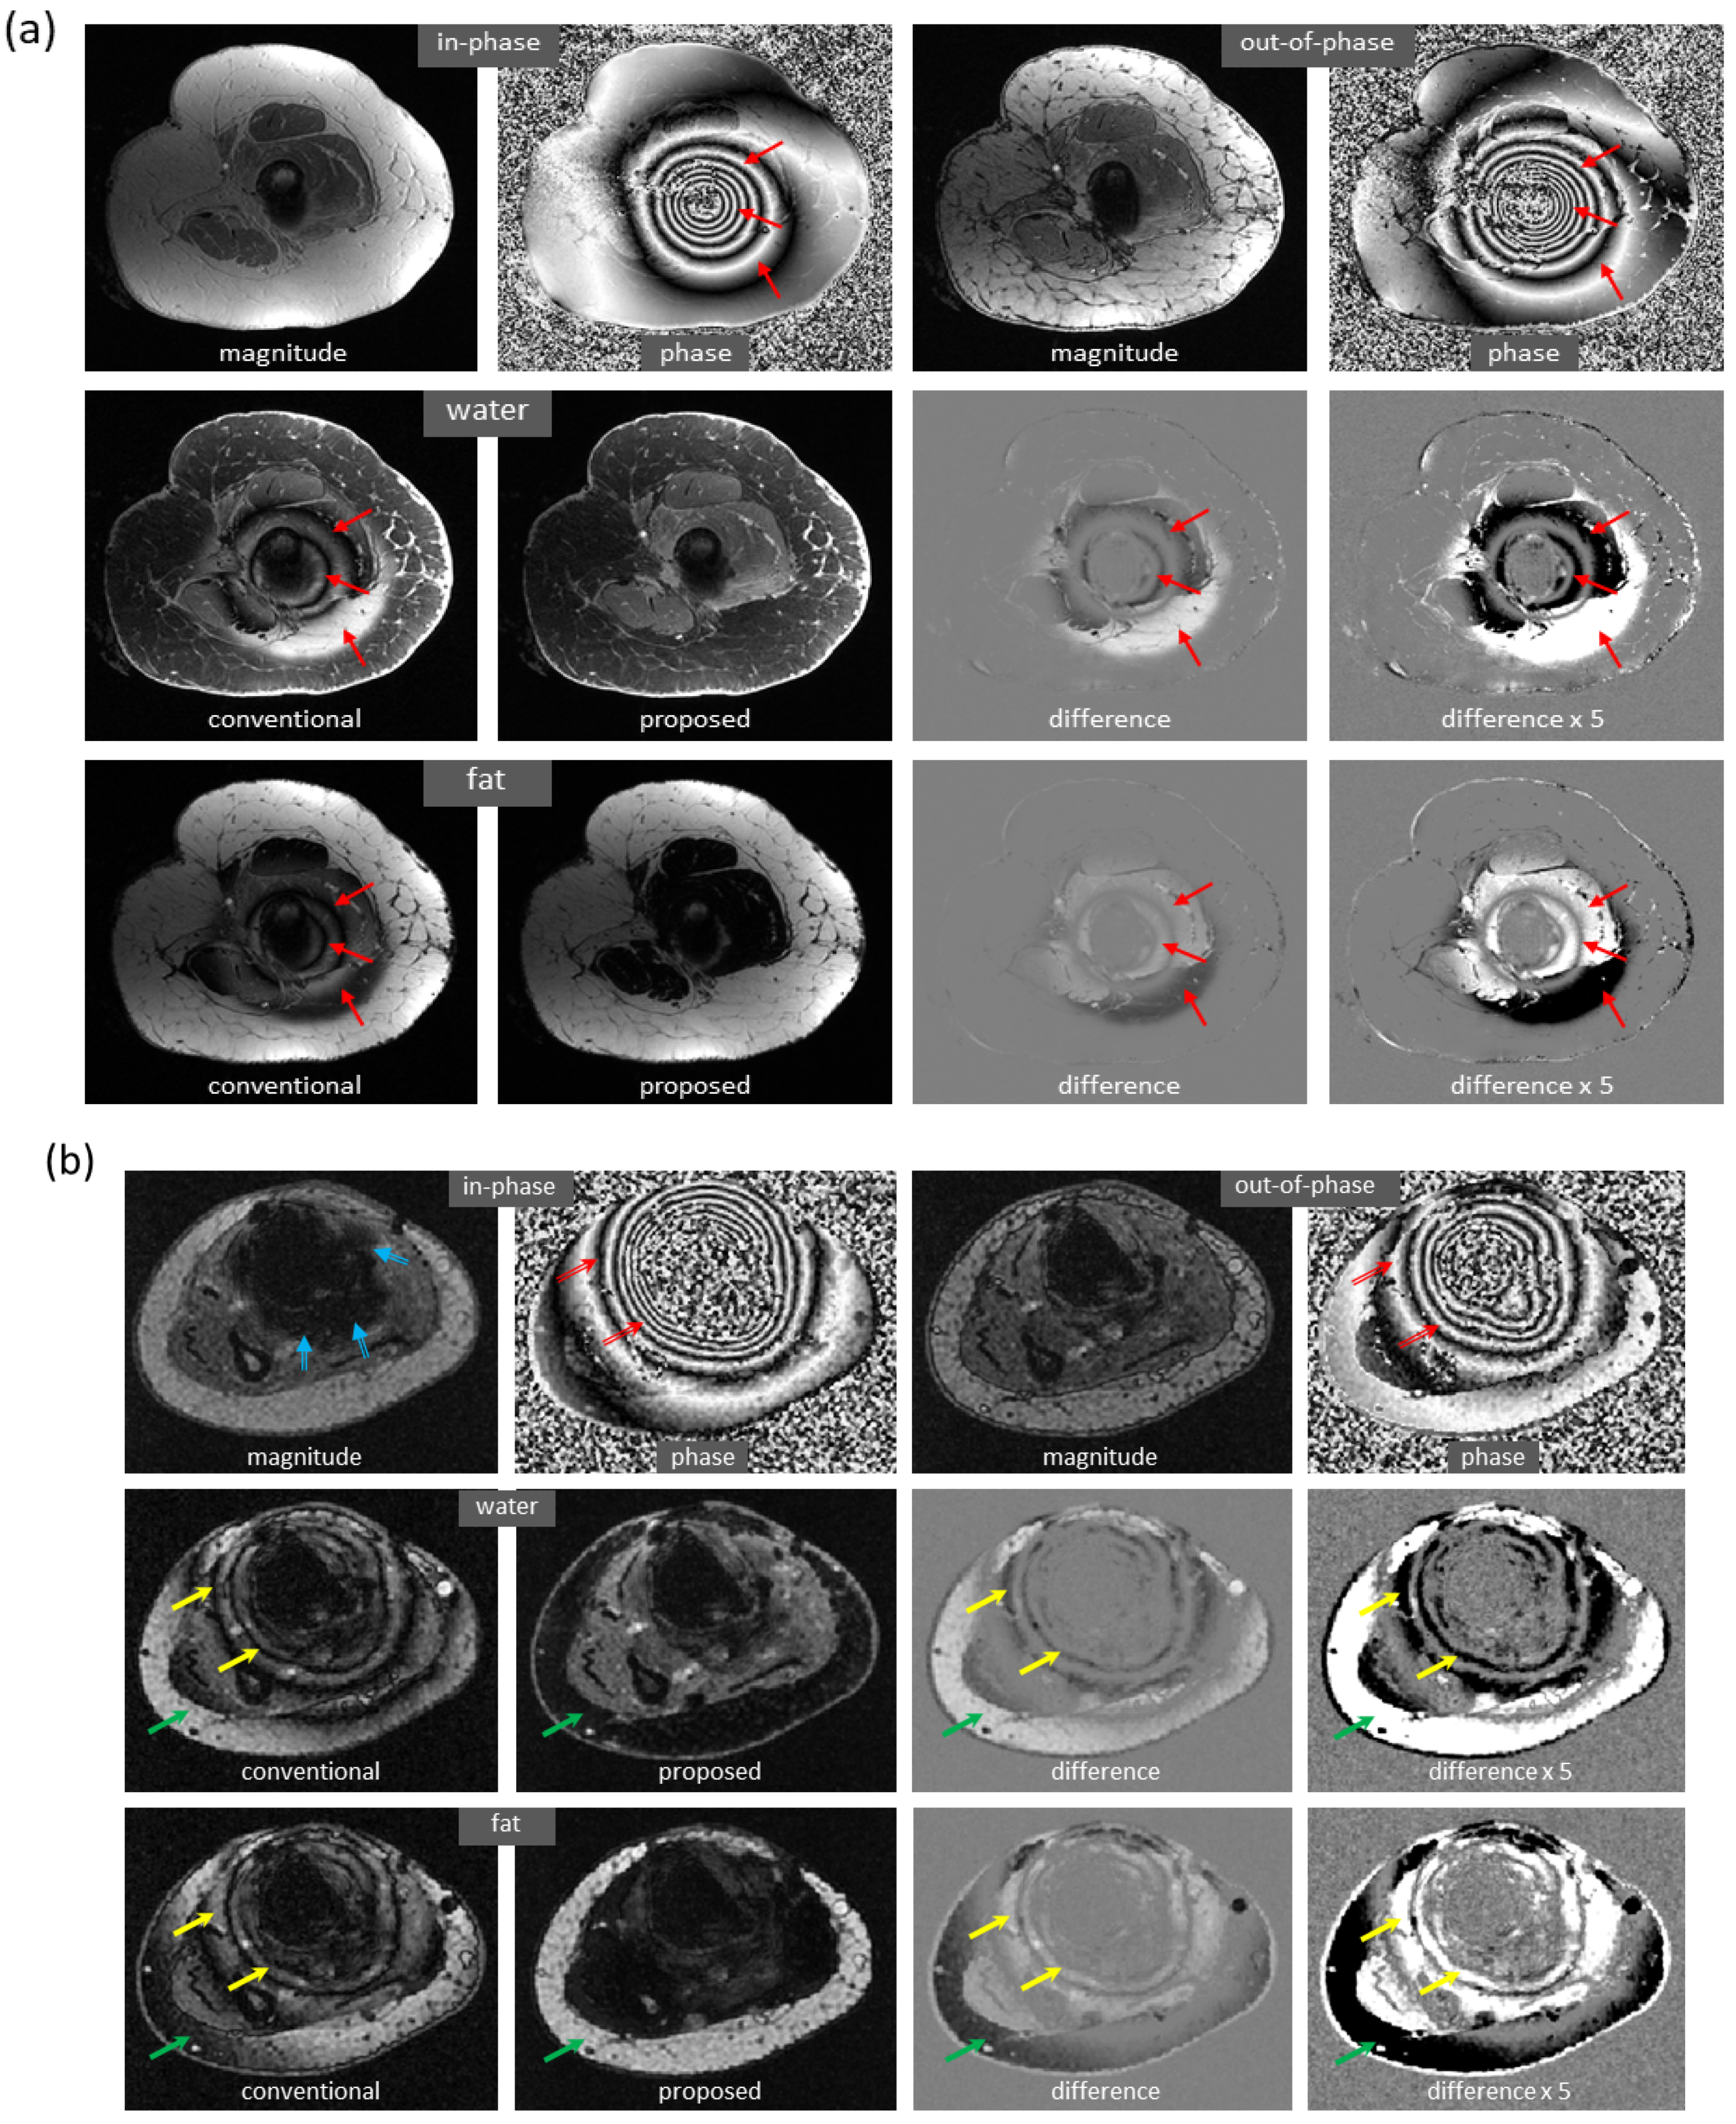

Water and fat images derived using the proposed method have high fidelity to the reference images. An example of the knee is demonstrated in Figure 3a. The differences between the predicted and reference images were negligible. In the predicted image, the enhancing tumors were well delineated. It is of note that this test set was acquired on a PET-MRI scanner (whereas the majority of the training data were obtained on MRI scanners). The models trained with only knee images also work well on out-of-distribution data from the foot, ankle, and arm. An example of the foot is demonstrated in Figure 3b (here, the images had a high spatial resolution that is not routinely obtained with dual-echo gradient echo imaging).

Figure 3.

High fidelity achieved in dual-echo water–fat separation (only water images are shown). (a) Using a well-trained deep learning model, highly accurate water images of the knee were predicted from in-phase and out-of-phase images (as well as echo times, not shown in the figure). The enhancing tumors (arrows) were well delineated. Notably, this test set was acquired on a PET-MRI scanner. (b) Using a deep learning model trained with only knee images, the predicted image of the foot has achieved high fidelity to the reference image, despite inference on a different anatomic region.

More examples with severe local water/fat swaps as well as global water/fat swaps are shown in Figure 5. In an ankle examination (Figure 5a), as the slices moved farther from isocenter, progressively severe water/fat swaps occurred in the peripheral region of reference images; the water/fat swaps were corrected in the predicted images. In a foot examination (Figure 5b), severe water/fat swaps appeared in the reference images (the dashed arrow pointed to an accessory ossicle with edema, and a local swap appeared in its marrow); the predicted images only had a few smaller swaps. In a knee study (Figure 5c), global water/fat swaps occurred, which in fact was not uncommon in conventional water–fat separation. Using the proposed method, global water/fat swaps were eliminated, and a slightly improved spatial resolution was observed, which can be attributed to the use of convolution for upsampling (expected to outperform conventional upsampling processing).

Figure 5.

Marked correction of severe water/fat swaps. (a) In an examination of the ankle, progressively severe water/fat swaps occurred in the reference images as they moved farther from isocenter (every ninth slice is shown). In the predicted images, the water/fat swaps were completely corrected. (b) In an examination of the foot, severe water/fat swaps appeared in the peripheral region of the reference images, where the dashed arrow showed an accessory ossicle with marrow edema that also had a local swap in its marrow. The water/fat swaps were substantially compensated in the predicted images, which only had smaller regions of swaps (solid arrows). (c) Global water/fat swaps, which occurred in the reference image, were corrected using the proposed deep learning method. An improved spatial resolution was observed in the predicted image.

Figure 6 shows the mitigation of severe artifacts induced by a metallic object, further demonstrating robustness to out-of-distribution data. The dramatic changes in local magnetic fields made the cases with metallic implants very challenging. In a knee study (Figure 6a), phase corruption in dual-echo images caused severe artifacts in the reference water/fat images. Interestingly, the predicted images lacked these artifacts. Here, the test images were acquired on a PET-MRI scanner (whereas the majority of training data were obtained on MRI scanners). In an ankle case (Figure 6b), both signal loss and phase corruption were observed in dual-echo images, leading to artifacts in the reference images. The metal artifacts, along with additional water/fat swaps that occurred in peripheral region of off-isocenter slices, were corrected in the predicted images even though the ankle images were acquired on a 1.5T MRI scanner (while training data were obtained on 3T scanners). Of note, for these two cases, is the fact that the training sets lacked any examples with metallic implants.

Figure 6.

Marked reduction of metal-induced artifacts, where the training set lacked any examples with metallic implants. (a) In this knee case acquired on a PET-MRI scanner, severe off-resonance artifacts occurred in the reference images since the local magnetic field near metal changed dramatically (as can be seen from the input phase images). In the predicted images, metal-induced artifacts were largely corrected. (b) In another ankle case acquired on a 1.5T MRI scanner, signal loss (blue arrow) and phase corruption (red arrow) were observed in the input images, resulting in artifacts in the reference images (yellow arrow). In addition, severe water/fat swaps (green arrow) occurred in the peripheral region of this off-isocenter slice. Both metal artifacts and water/fat swaps were mitigated in the predicted images, even when the model was trained with only knee images acquired on 3T scanners.